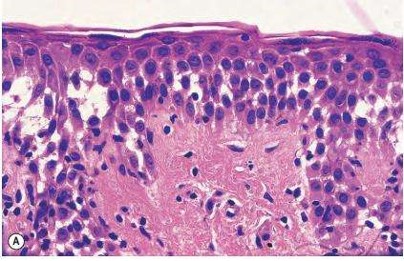

• 炎癥性皮膚病研究診治進入分子層面

銀屑病、特應性皮炎、濕疹是一組常見的慢性炎癥性皮膚病,據不完全統計,發病率在20%以上。由于確切的病因及發病機制尚未完全闡明,缺乏徹底治愈的臨床藥物,遷延難愈且復發率高。...